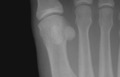

Gray284.png

The first metatarsal. (Left.)